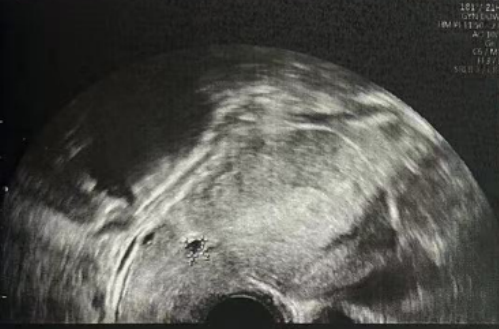

子宫内膜厚度:4.6 毫米,子宫有瘢痕大小 0.76*0.19 厘米

子宫内膜厚度:9.3-10 毫米

- 有粘液滞留在腔内,从峡部瘢痕延伸至子宫底

- 双卵巢无囊肿

- 计划在胚胎移植前重复超声检查以冲洗峡部瘢痕